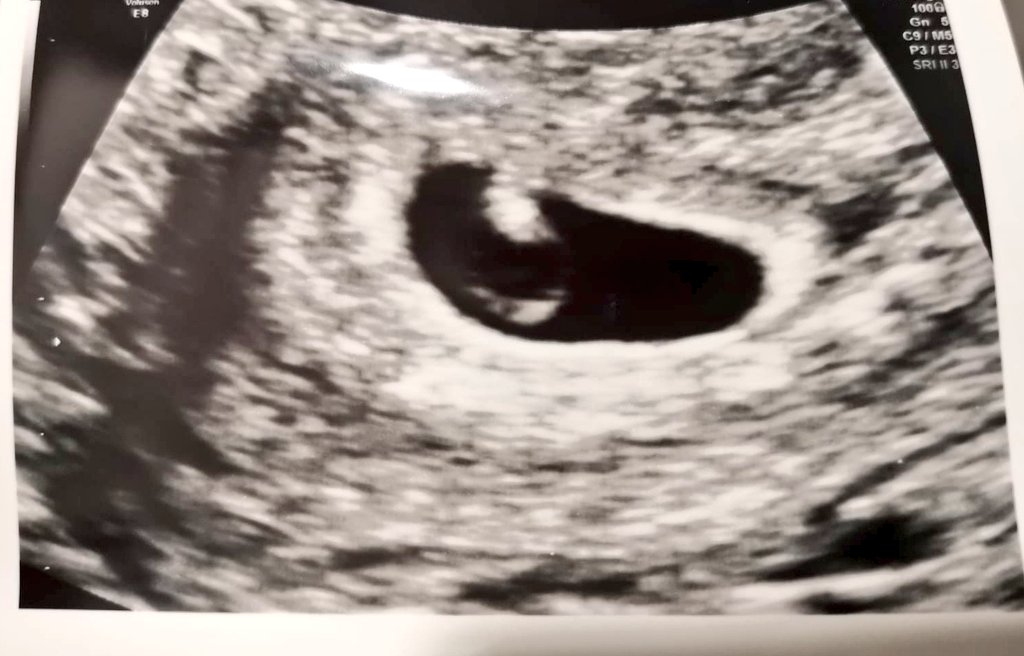

#6w1d it's very very early days but we got a heartbeat ❤️ today, we have been here before though, so cautious, but for today we are so very happy! #IVF5 #ET7 #embryos10and11 #pregnancyafterloss #malefactor #DNAfragmentation #ICSI #IMSI #PICSI #earlydays

9

0

83